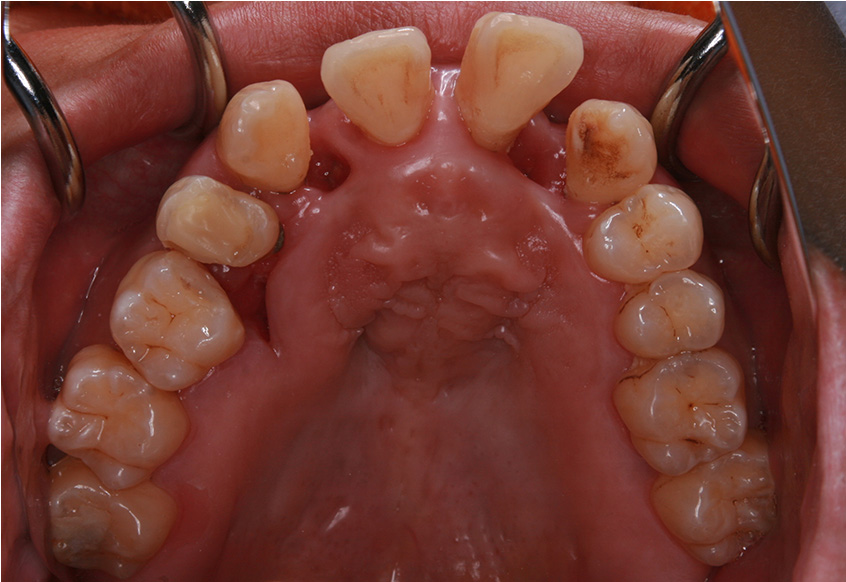

治療開始後3ヵ月経過すると、前歯の隙間や全体の乱れが減ってきました。口笛が吹けるようになったとのことです。

最初のお口の中 治療開始3ヵ月後